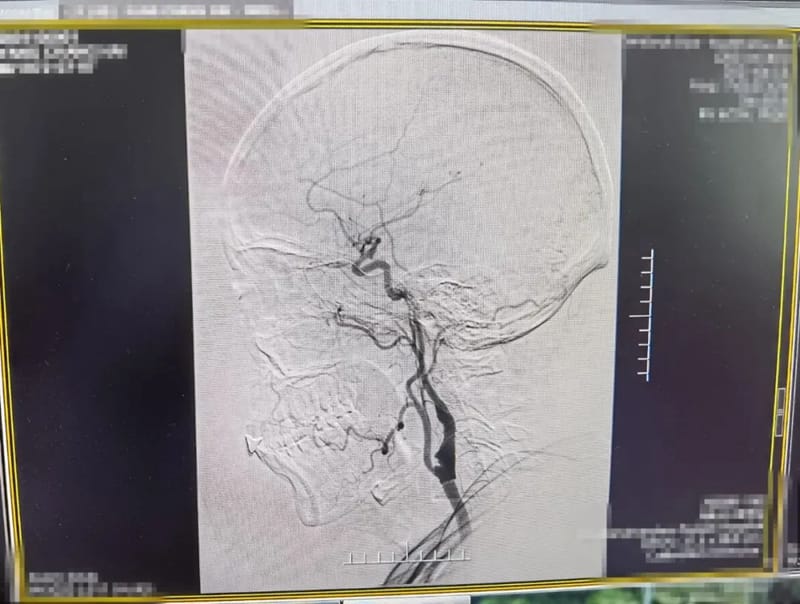

术后造影颈内动脉狭窄明显改善